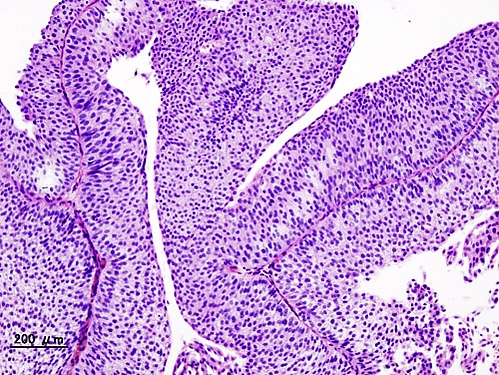

Bladder urothelial carcinoma (1) pT1.JPG

Самой распространённой формой рака мочевого пузыря является переходноклеточный рак (развивающийся из переходного эпителия мочевых путей), более редко встречаются плоскоклеточный рак и аденокарцинома (опухоль, происходящая и построенная из железистого эпителия). Болезнь может проявляться в виде папиллярных разрастаний (нелинейные пристеночные включения) с малигнизацией или солидной, изъязвлённой, инвазирующей опухоли. Различают рак мочевого пузыря in situ, поверхностный рак (Т1-2) и рак, инвазирующий мышечный слой и окружающие ткани (ТЗ-4).